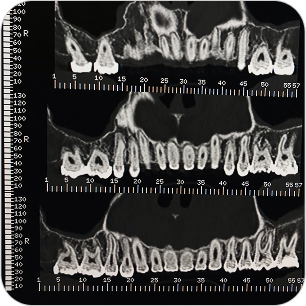

Dental Scan (Tomografía 3D Dental)

El Dental Scan o Tomografía Computada de Haz Cónico (CBCT) es un estudio especializado que brinda imágenes tridimensionales de alta resolución del sistema dentomaxilofacial. Es fundamental en odontología avanzada, permitiendo planificaciones precisas y diagnósticos más seguros.

La tomografía dental (CBCT) es un estudio esencial en odontología avanzada, que permite ver el maxilar, mandíbula y piezas dentales en 3D para diagnósticos y tratamientos más seguros.

¿PARA QUÉ SE UTILIZA?

- Planificación de implantes dentales con medición exacta del hueso.

- Evaluación de muelas del juicio o dientes incluidos.

- Estudio de quistes, tumores o lesiones óseas de mandíbula y maxilar.

- Diagnóstico de patología articular (ATM).

- Detección de fracturas, reabsorciones o infecciones profundas.

- Cirugías ortognáticas y procedimientos maxilofaciales complejos.

¿POR QUÉ ES UN ESTUDIO DESTACADO?

- Imágenes en 3D reales y de alta definición.

- Mucho más preciso que una radiografía panorámica tradicional.

- Estudio rápido, cómodo y con baja dosis de radiación.

Dental Scan (Tomografía 3D Dental)

El Dental Scan o Tomografía Computada de Haz Cónico (CBCT) es un estudio especializado que brinda imágenes tridimensionales de alta resolución del sistema dentomaxilofacial. Es fundamental en odontología avanzada, permitiendo planificaciones precisas y diagnósticos más seguros.

La tomografía dental (CBCT) es un estudio esencial en odontología avanzada, que permite ver el maxilar, mandíbula y piezas dentales en 3D para diagnósticos y tratamientos más seguros.

¿PARA QUÉ SE UTILIZA?

- Planificación de implantes dentales con medición exacta del hueso.

- Evaluación de muelas del juicio o dientes incluidos.

- Estudio de quistes, tumores o lesiones óseas de mandíbula y maxilar.

- Diagnóstico de patología articular (ATM).

- Detección de fracturas, reabsorciones o infecciones profundas.

- Cirugías ortognáticas y procedimientos maxilofaciales complejos.

¿POR QUÉ ES UN ESTUDIO DESTACADO?

- Imágenes en 3D reales y de alta definición.

- Mucho más preciso que una radiografía panorámica tradicional.

- Estudio rápido, cómodo y con baja dosis de radiación.